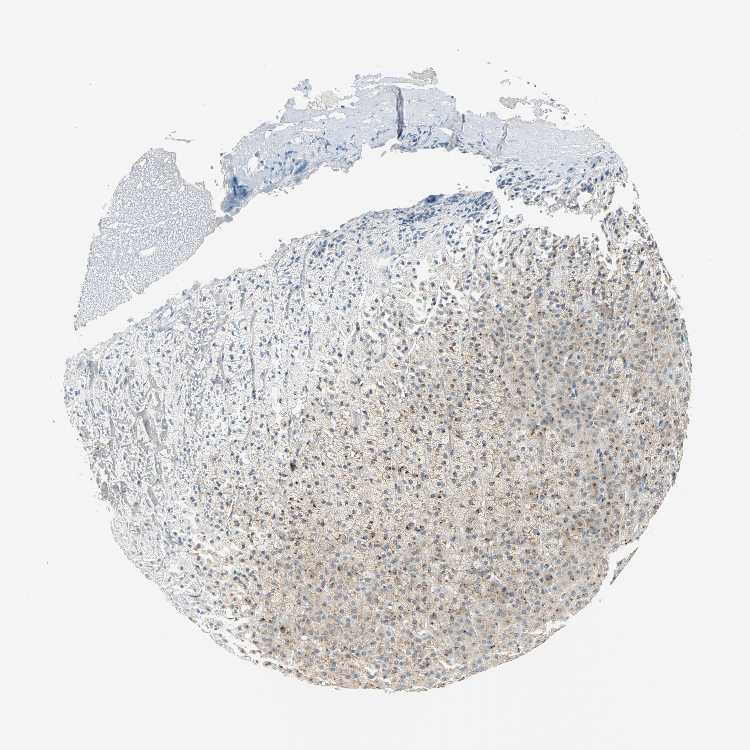

ADRENAL GLAND - Antibody stainingi

Antibody staining in the annotated cell types in the current human tissue is reported as not detected, low, medium, or high, based on conventional immunohistochemistry profiling in selected tissues. This score is based on the combination of the staining intensity and fraction of stained cells.

Each image is clickable and will lead to virtual microscopy that enables deeper exploration of all samples and also displays staining intensity scores, fraction scores and subcellular localization as well as patient and tissue information for each sample.

Antibody CAB006254

Glandular cells High